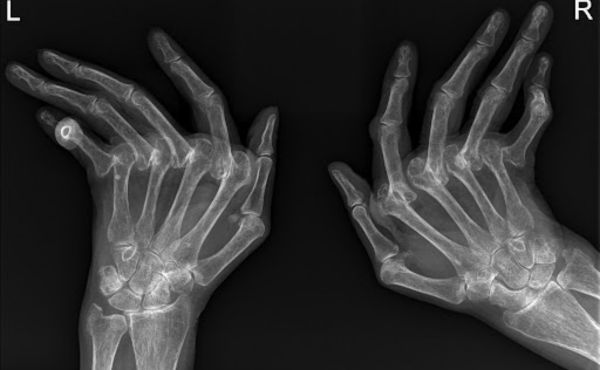

D. Diagnostyka obrazowa (RTG, USG, MRI)

Obrazowe badania diagnostyczne takie jak rentgen (RTG), ultrasonografia (USG) czy rezonans magnetyczny (MRI) mogą pomóc w ocenie uszkodzeń stawów, stanu zapalnego oraz zmian zwyrodnieniowych.

A. Uszkodzenia stawów i deformacje

RZS może prowadzić do uszkodzenia i zniszczenia stawów, co może doprowadzić do trwałych deformacji. Charakterystyczne objawy to zniekształcenie palców rąk w postaci „kurzych palców” lub „świdrujących palców”. Regularne monitorowanie stanu stawów i odpowiednie leczenie mogą pomóc w ograniczeniu uszkodzeń i deformacji.